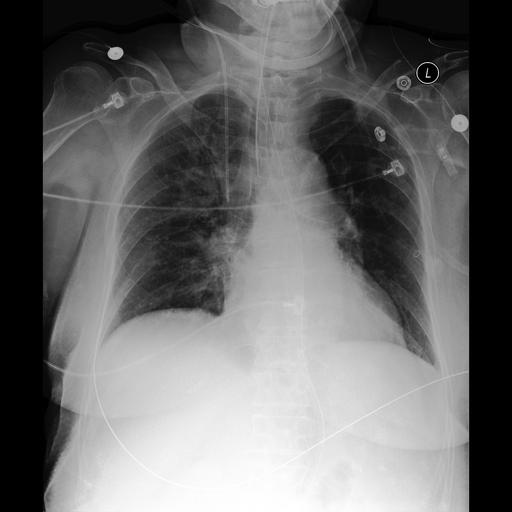

Table 4 shows a Zero-Shot example on MIMIC-CXR that reflects the error patterns observed in Table 2. The ground truth report describes multiple devices (endotracheal tube, orogastric tube, right internal jugular catheter), low lung volumes, and a right upper lobe opacity suspicious for pneumonia, explicitly ruling out pleural effusion and pneumothorax.

Table 4: Qualitative Comparison in Zero-Shot Setting for LLaVA-Med. Highlighting indicates: incorrect/hallucinated findings, incomplete descriptions, superfluous details, accurate content.

Zero-Shot Setting

Chest X-Ray Image Ground Truth Report

[Uncaptioned image] Endotracheal tube terminates 2 cm above the carina. Orogastric tube terminates in the stomach. Right internal jugular catheter terminates in the mid SVC. Lungs are low in volume with stable right upper lung opacities which are better assessed on the recent chest CT but suspicious for pneumonia. There is no pneumothorax or pleural effusion. Heart is normal in size. Normal cardiomediastinal silhouette.

SpLiCE Concepts: pulmonary vascularity, overt pulmonary, right upper, endotracheal tube, internal jugular

Image-Only The chest X-ray image shows bilateral diffuse infiltrates, which are abnormal substances or collections of cells that have entered the lung tissue. These infiltrates can be seen in both lungs and are distributed throughout the lung fields.

+ Concepts The chest X-ray shows overt pulmonary edema, which is a condition where there is an abnormal accumulation of fluid in the lungs. Additionally, there is a right upper lobe opacity, which could be due to various reasons such as infection, inflammation, or other lung abnormalities. The internal jugular vein is visible, and an endotracheal tube is in place, which is a tube that is inserted through the mouth or nose and into the trachea to help maintain an open airway and assist with breathing. Lastly, the pulmonary vascularity appears to be normal.

+ RAG The chest X-ray findings are similar to those in the earlier study. The main differences observed are the placement of a left IJ catheter and the presence of an indistinct area of opacification in the right upper zone medially, which could represent a developing consolidation. Additionally, there is a right IJ central venous catheter with its tip at the lower SVC near the cavoatrial junction, and the endotracheal tube has been slightly advanced. No pneumothorax is noted. Pulmonary vascular congestion is observed.

+ CEMRAG In the right upper zone, there is an indistinct area of opacification, which could represent a developing consolidation. Additionally, there is a right internal jugular central venous catheter with its tip at the lower superior vena cava near the cavoatrial junction. The endotracheal tube has been slightly advanced, with its tip 2.2 cm above the carina. No pneumothorax is noted, and the pulmonary vascular congestion is present. The cardiomediastinal silhouette remains unchanged.

The baseline LLaVA-Med model produces a markedly incorrect description, hallucinating bilateral diffuse infiltrates and failing to mention any of the indwelling devices, in line with the very low Zero-Shot F1-RG observed quantitatively. This behaviour indicates that, without additional guidance, the model tends to generate generic patterns of abnormality that are not well grounded in the specific image. With Concepts augmentation, all extracted keywords (e.g., “endotracheal tube”, “internal jugular”, “right upper”) are explicitly mentioned in the generated text, and the report correctly identifies both the endotracheal tube and a right upper lobe opacity. However, the model now over-interprets the concept set by asserting overt pulmonary edema, a finding not present in the reference report. This illustrates how SpLiCE decomposition can substantially increase CheXbert Micro-F1 by encouraging the mention of clinically salient terms, while still lagging behind retrieval-based strategies on metrics that reward correct entity–relation structure. Notably, the model produces verbose explanations of medical concepts (e.g., describing what an endotracheal tube does), as LLaVA-Med’s general medical pretraining has not been adapted to the concise technical language conventions of radiology reports. RAG-only reduces some of these concept-driven hallucinations but introduces others. Conditioning on retrieved in-domain reports leads the model to blend details from similar but non-identical cases, such as mentioning a left internal jugular catheter and pulmonary vascular congestion that are not supported by the target image. This exemplifies a typical retrieval-induced failure mode in which information from nearest neighbours leaks into the generated report. The combined CEMRAG condition achieves the most clinically plausible description. It correctly identifies the right internal jugular catheter, the endotracheal tube position, and the right upper zone opacity, and avoids the more severe hallucinations observed in the RAG-only report, although it still mentions mild vascular congestion. This example mirrors the quantitative trends: concept cues alone can act as over-strong priors, and retrieval alone can import spurious details, whereas their combination yields better grounded descriptions that more closely match the reference report.